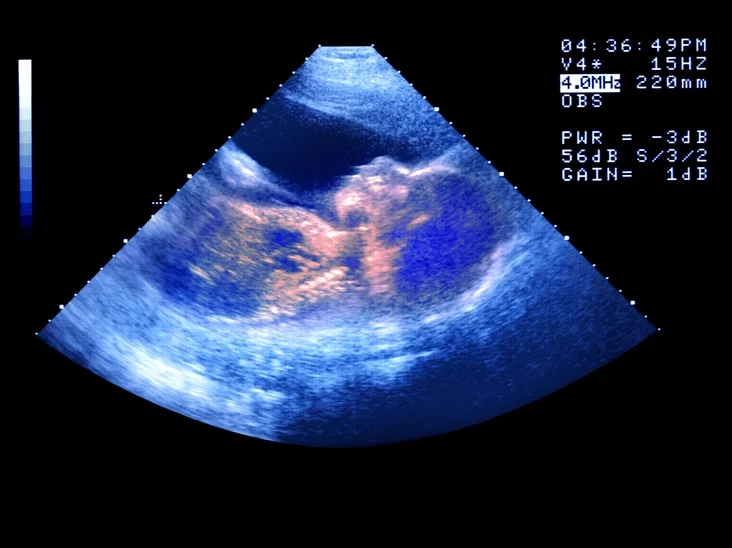

Repraduktyŭnyja technałohii niaspynna ŭdaskanalvajucca i ŭžo źmianili sposab stvareńnia siamji. Bolš za 40 hadoŭ tamu sapraŭdnaj revalucyjaj stała technałohija EKA (ekstrakarparalnaha apładnieńnia) — vyviadzieńnia śpiełych jajcakletak ź jaječnikaŭ, ich apładnieńnie ŭ łabaratoryi i impłantacyja embryjona ŭ matku.

Pracedura EKA razarvała suviaź pamiž jajcakletkami i maciarynstvam. Jak maci možna identyfikavać i žančynu, jakaja dała jajcakletku, i žančynu, jakaja naradziła abo vyhadavała dzicia. Akramia taho, EKA dało vialikuju repraduktyŭnuju aŭtanomiju niekatorym pradstaŭnikam ŁHBTK.